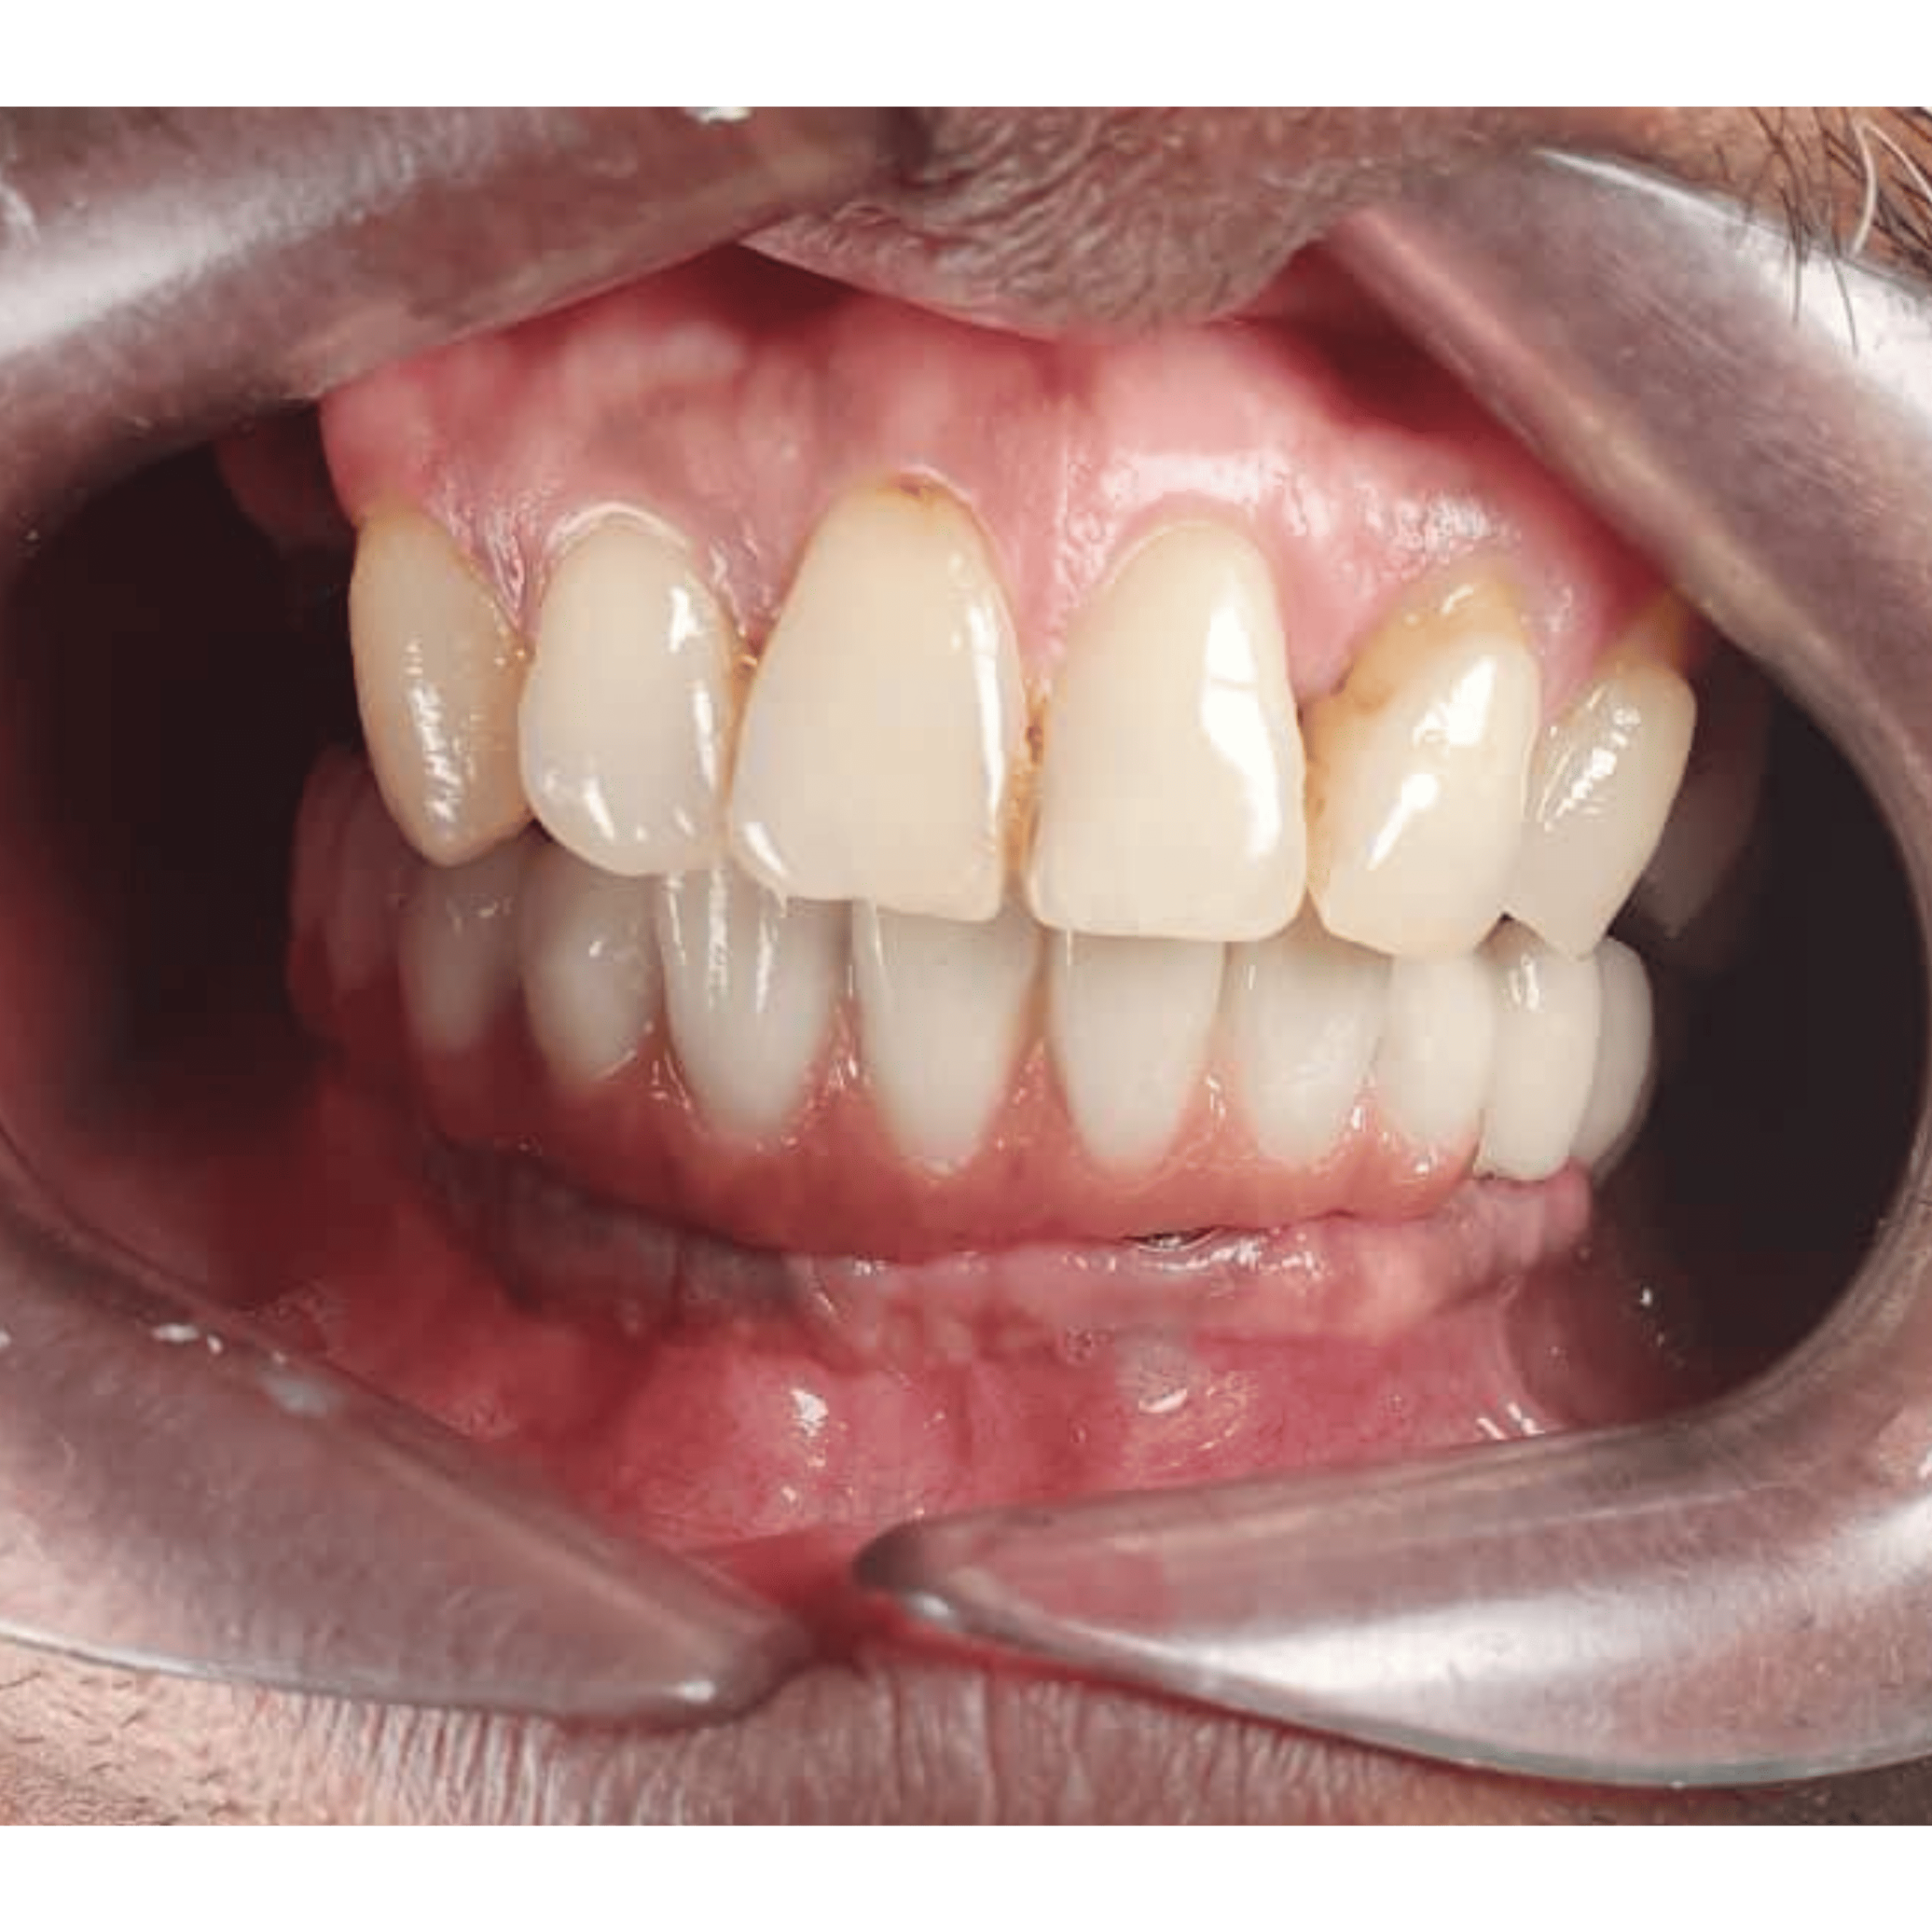

Before & After

📸 Before: Visible gap between teeth

📸 After: Implant crown blends naturally with other teeth